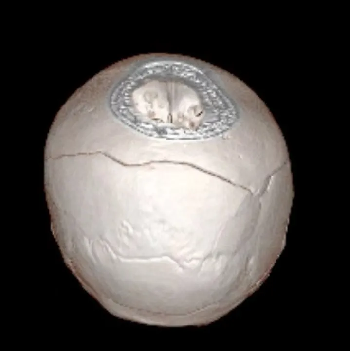

術前: